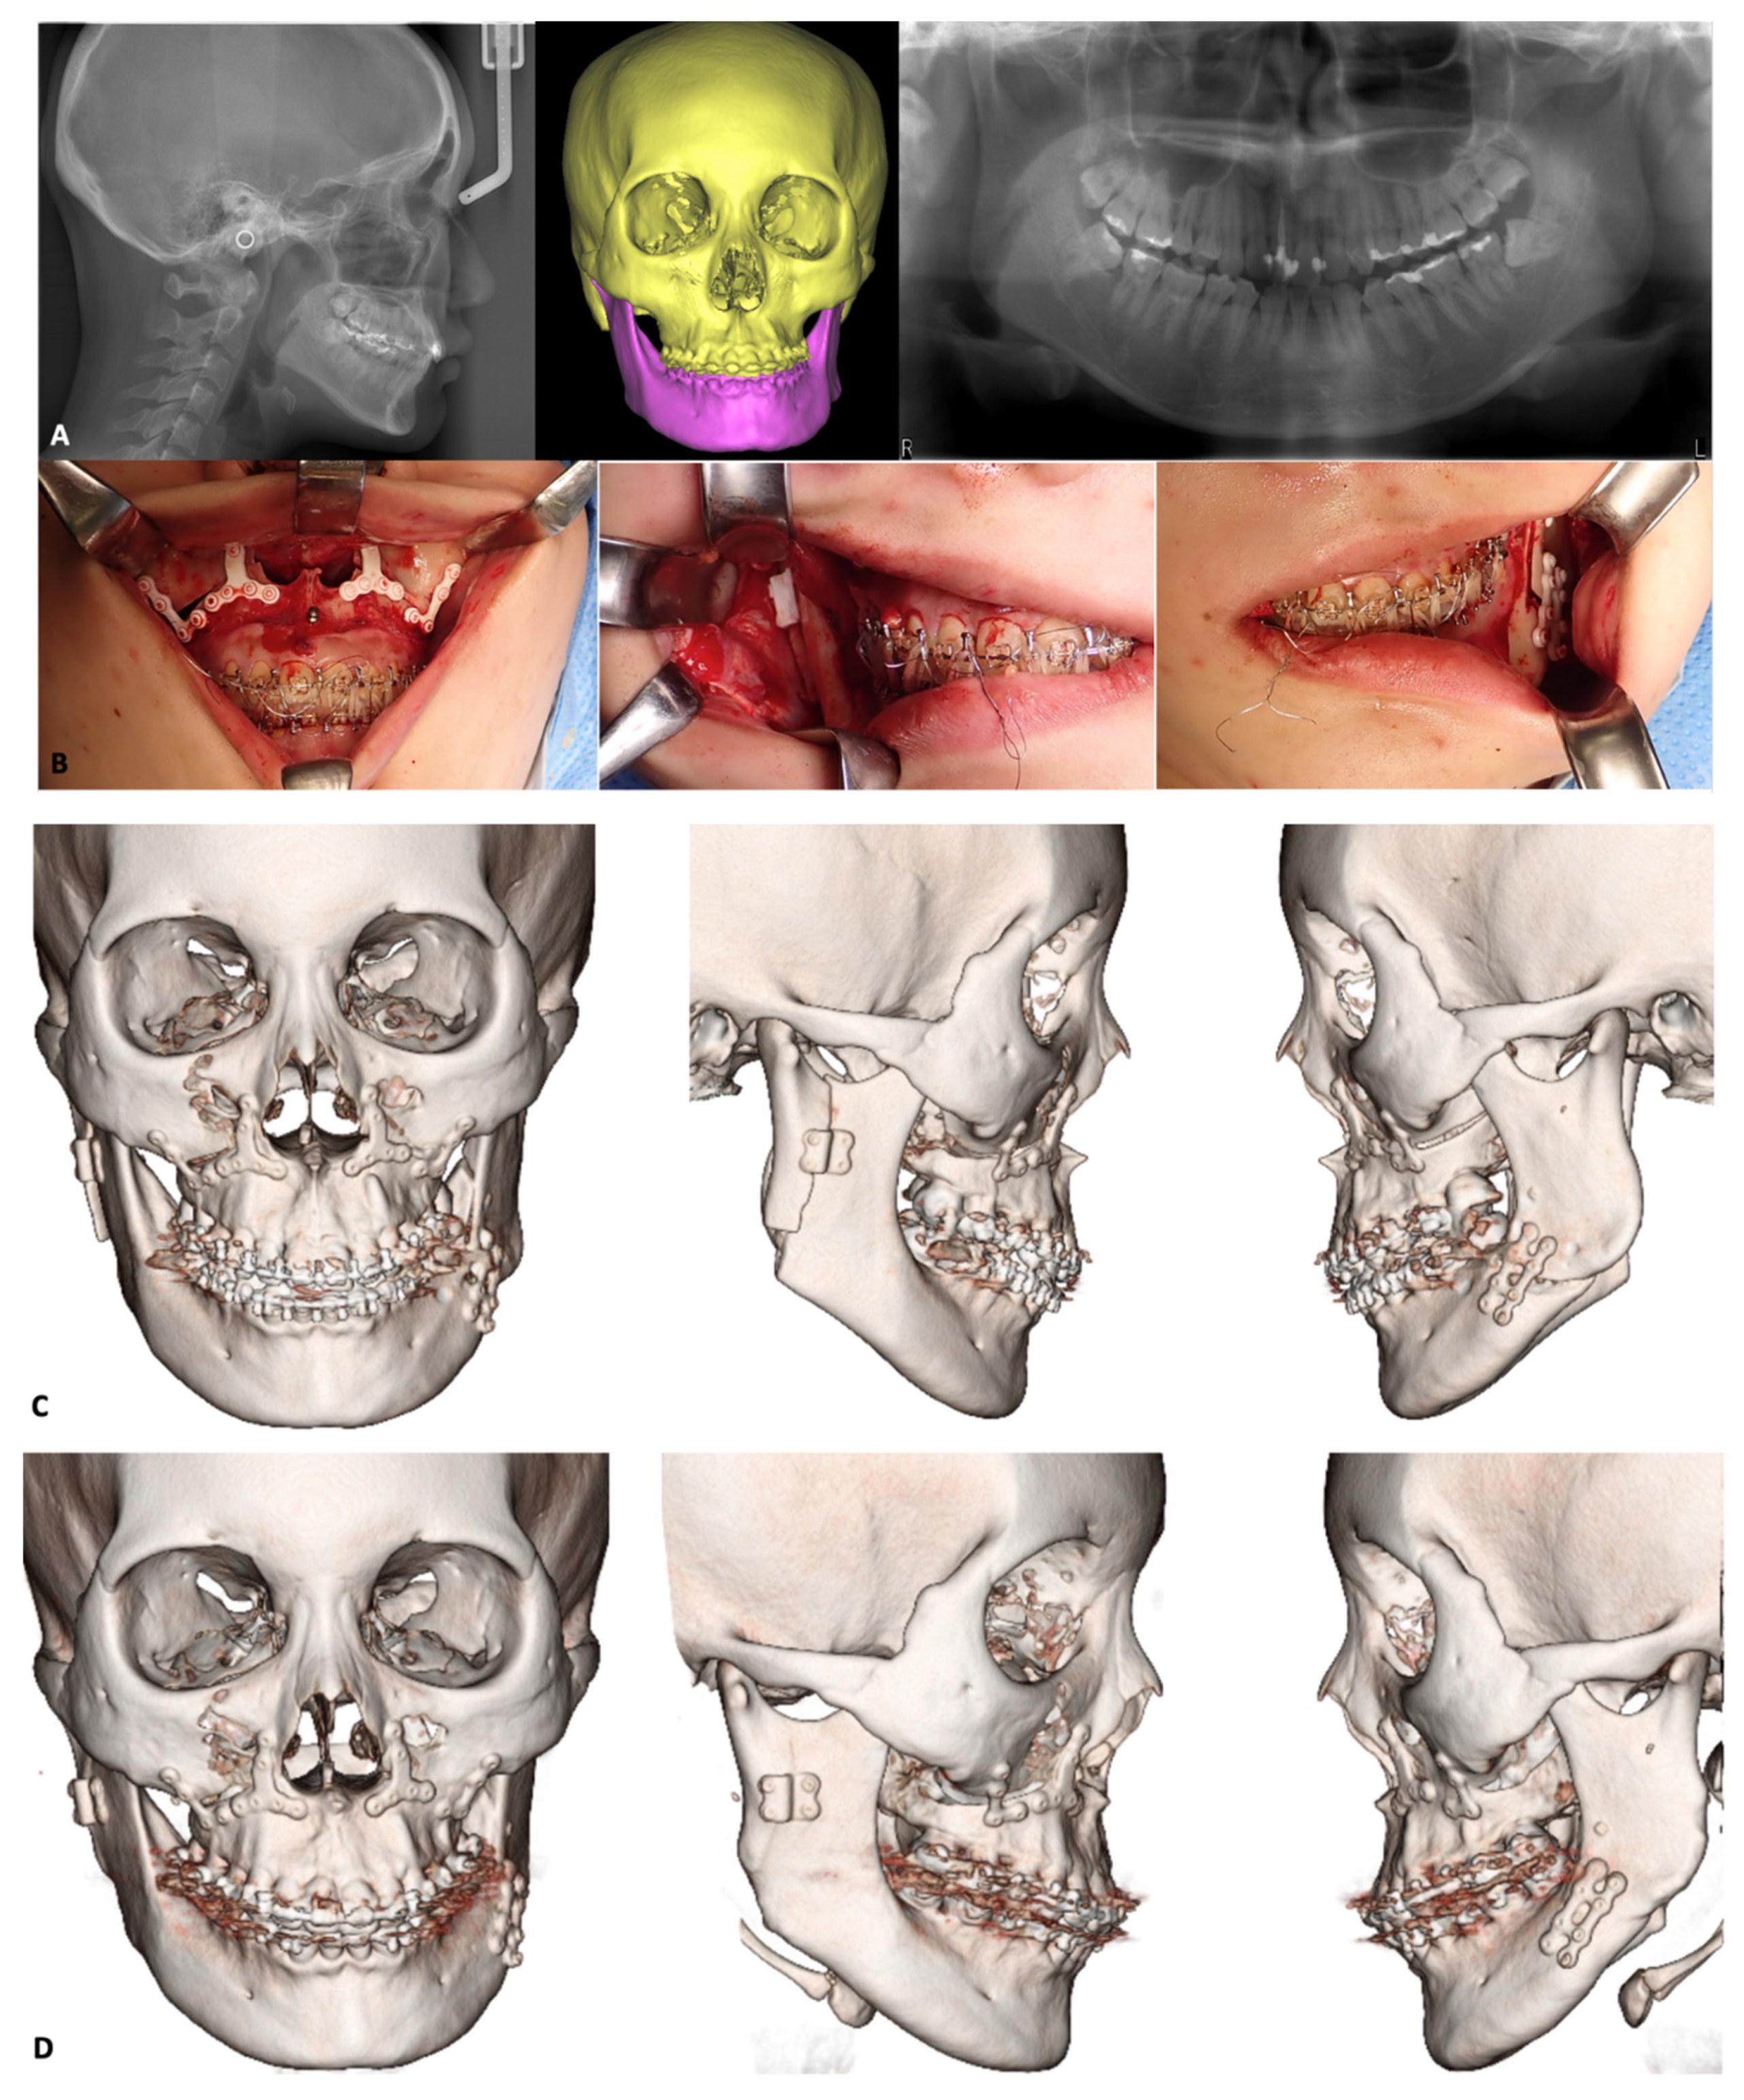

3.2. Orthognathic Surgery

3.2.1. Le Fort I osteotomy

3.2.2. Mandibular Osteotomies

- Ueki, K.; Miyazaki, M.; Okabe, K.; Mukozawa, A.; Marukawa, K.; Moroi, A.; Nakagawa, K.; Yamamoto, E. Assessment of bone healing after Le Fort I osteotomy with 3-dimensional computed tomography. J. Cranio-Maxillofacial Surg. 2011, 39, 237–243. [Google Scholar] [CrossRef] [PubMed] [Green Version]

- Ueki, K.; Okabe, K.; Moroi, A.; Marukawa, K.; Sotobori, M.; Ishihara, Y.; Nakagawa, K. Maxillary stability after Le Fort I osteotomy using three different plate systems. Int. J. Oral Maxillofac. Surg. 2012, 41, 942–948. [Google Scholar] [CrossRef] [PubMed] [Green Version]

- Ueki, K.; Okabe, K.; Marukawa, K.; Mukozawa, A.; Moroi, A.; Miyazaki, M.; Sotobori, M.; Ishihara, Y.; Yoshizawa, K.; Ooi, K.; et al. Maxillary stability after Le Fort I osteotomy with self-setting α-tricalcium phosphate and an absorbable plate. Int. J. Oral Maxillofac. Surg. 2013, 42, 597–603. [Google Scholar] [CrossRef] [PubMed] [Green Version]

- Ueki, K.; Yoshizawa, K.; Moroi, A.; Hotta, A.; Tsutsui, T.; Fukaya, K.; Hiraide, R.; Takayama, A.; Tsunoda, T.; Saito, Y.; et al. Evaluation of maxillary sinus after Le Fort I osteotomy using various fixation materials. J. Cranio-Maxillofacial Surg. 2017, 45, 552–557. [Google Scholar] [CrossRef] [PubMed]

- Ueki, K.; Okabe, K.; Miyazaki, M.; Mukozawa, A.; Moroi, A.; Marukawa, K.; Nakagawa, K.; Yamamoto, E. Skeletal stability after mandibular setback surgery: Comparisons among unsintered hydroxyapatite/poly-L-lactic acid plate, poly-L-lactic acid plate, and titanium plate. J. Oral Maxillofac. Surg. 2011, 69, 1464–1468. [Google Scholar] [CrossRef] [PubMed] [Green Version]

- Sukegawa, S.; Kanno, T.; Manabe, Y.; Matsumoto, K.; Sukegawa-Takahashi, Y.; Masui, M.; Furuki, Y. Biomechanical Loading Evaluation of Unsintered Hydroxyapatite/poly-l-lactide Plate System in Bilateral Sagittal Split Ramus Osteotomy. Materials 2017, 10, 764. [Google Scholar] [CrossRef] [Green Version]

- Park, Y.-W.; Kang, H.-S.; Lee, J.-H. Comparative study on long-term stability in mandibular sagittal split ramus osteotomy: Hydroxyapatite/poly-l-lactide mesh versus titanium miniplate. Maxillofac. Plast. Reconstr. Surg. 2019, 41, 8. [Google Scholar] [CrossRef] [PubMed] [Green Version]